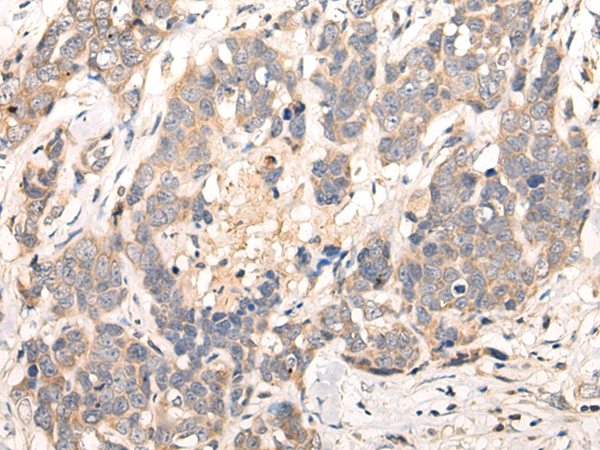

IHC positive control:

Human thyroid cancer and human ovarian cancer